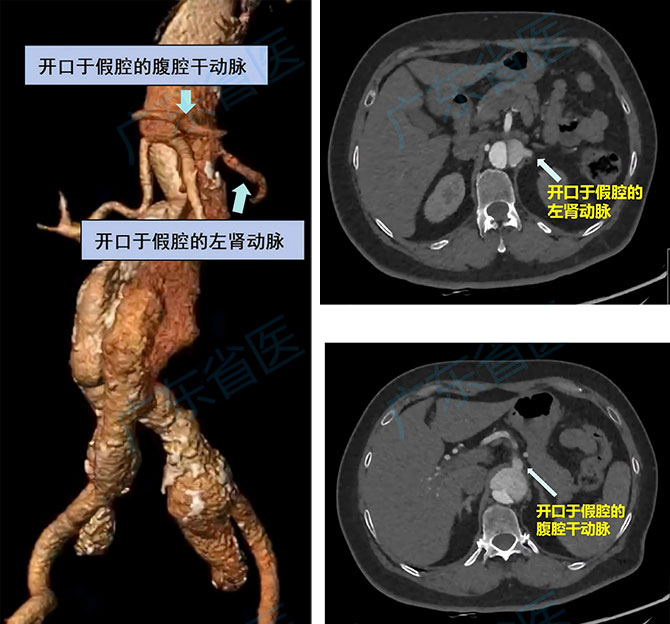

第一关:打通“真假通道”。张阿姨的左肾动脉和腹腔干动脉的开口在假腔里,真腔与假腔之间既有增厚内膜,又覆有既往支架的密实膜层,手术时得在这两层屏障上精准打孔,建立通道,才能把支架送进动脉,不然肝、肾很快就会缺血出问题。

3. 用“原位穿刺”技术,先后扎两针,分别重建左肾动脉和腹腔干动脉,扎针成功后把通道扩张开,放入鞘管、导丝和小支架。